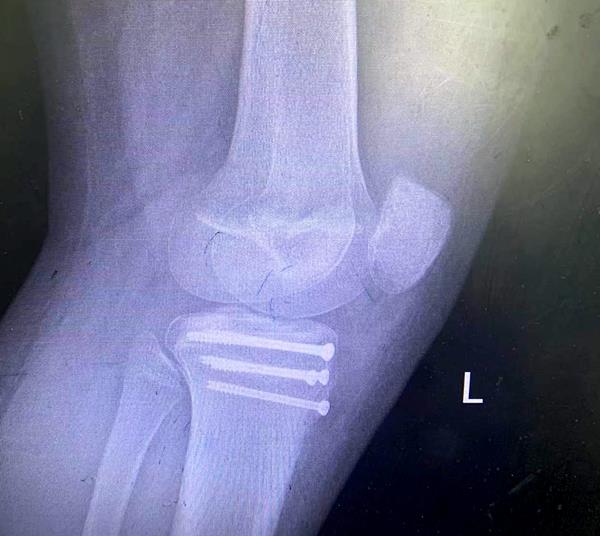

患者成功手術(shù)后的影像

這次收治的患者屬于Ogden 3A型,手術(shù)指征明確,手術(shù)團隊采用骨折端切開復位空心釘內(nèi)固定+髕韌帶可吸收錨釘重建術(shù)+經(jīng)膝關(guān)節(jié)鏡探查、清理的手術(shù)方式,獲得滿意效果。